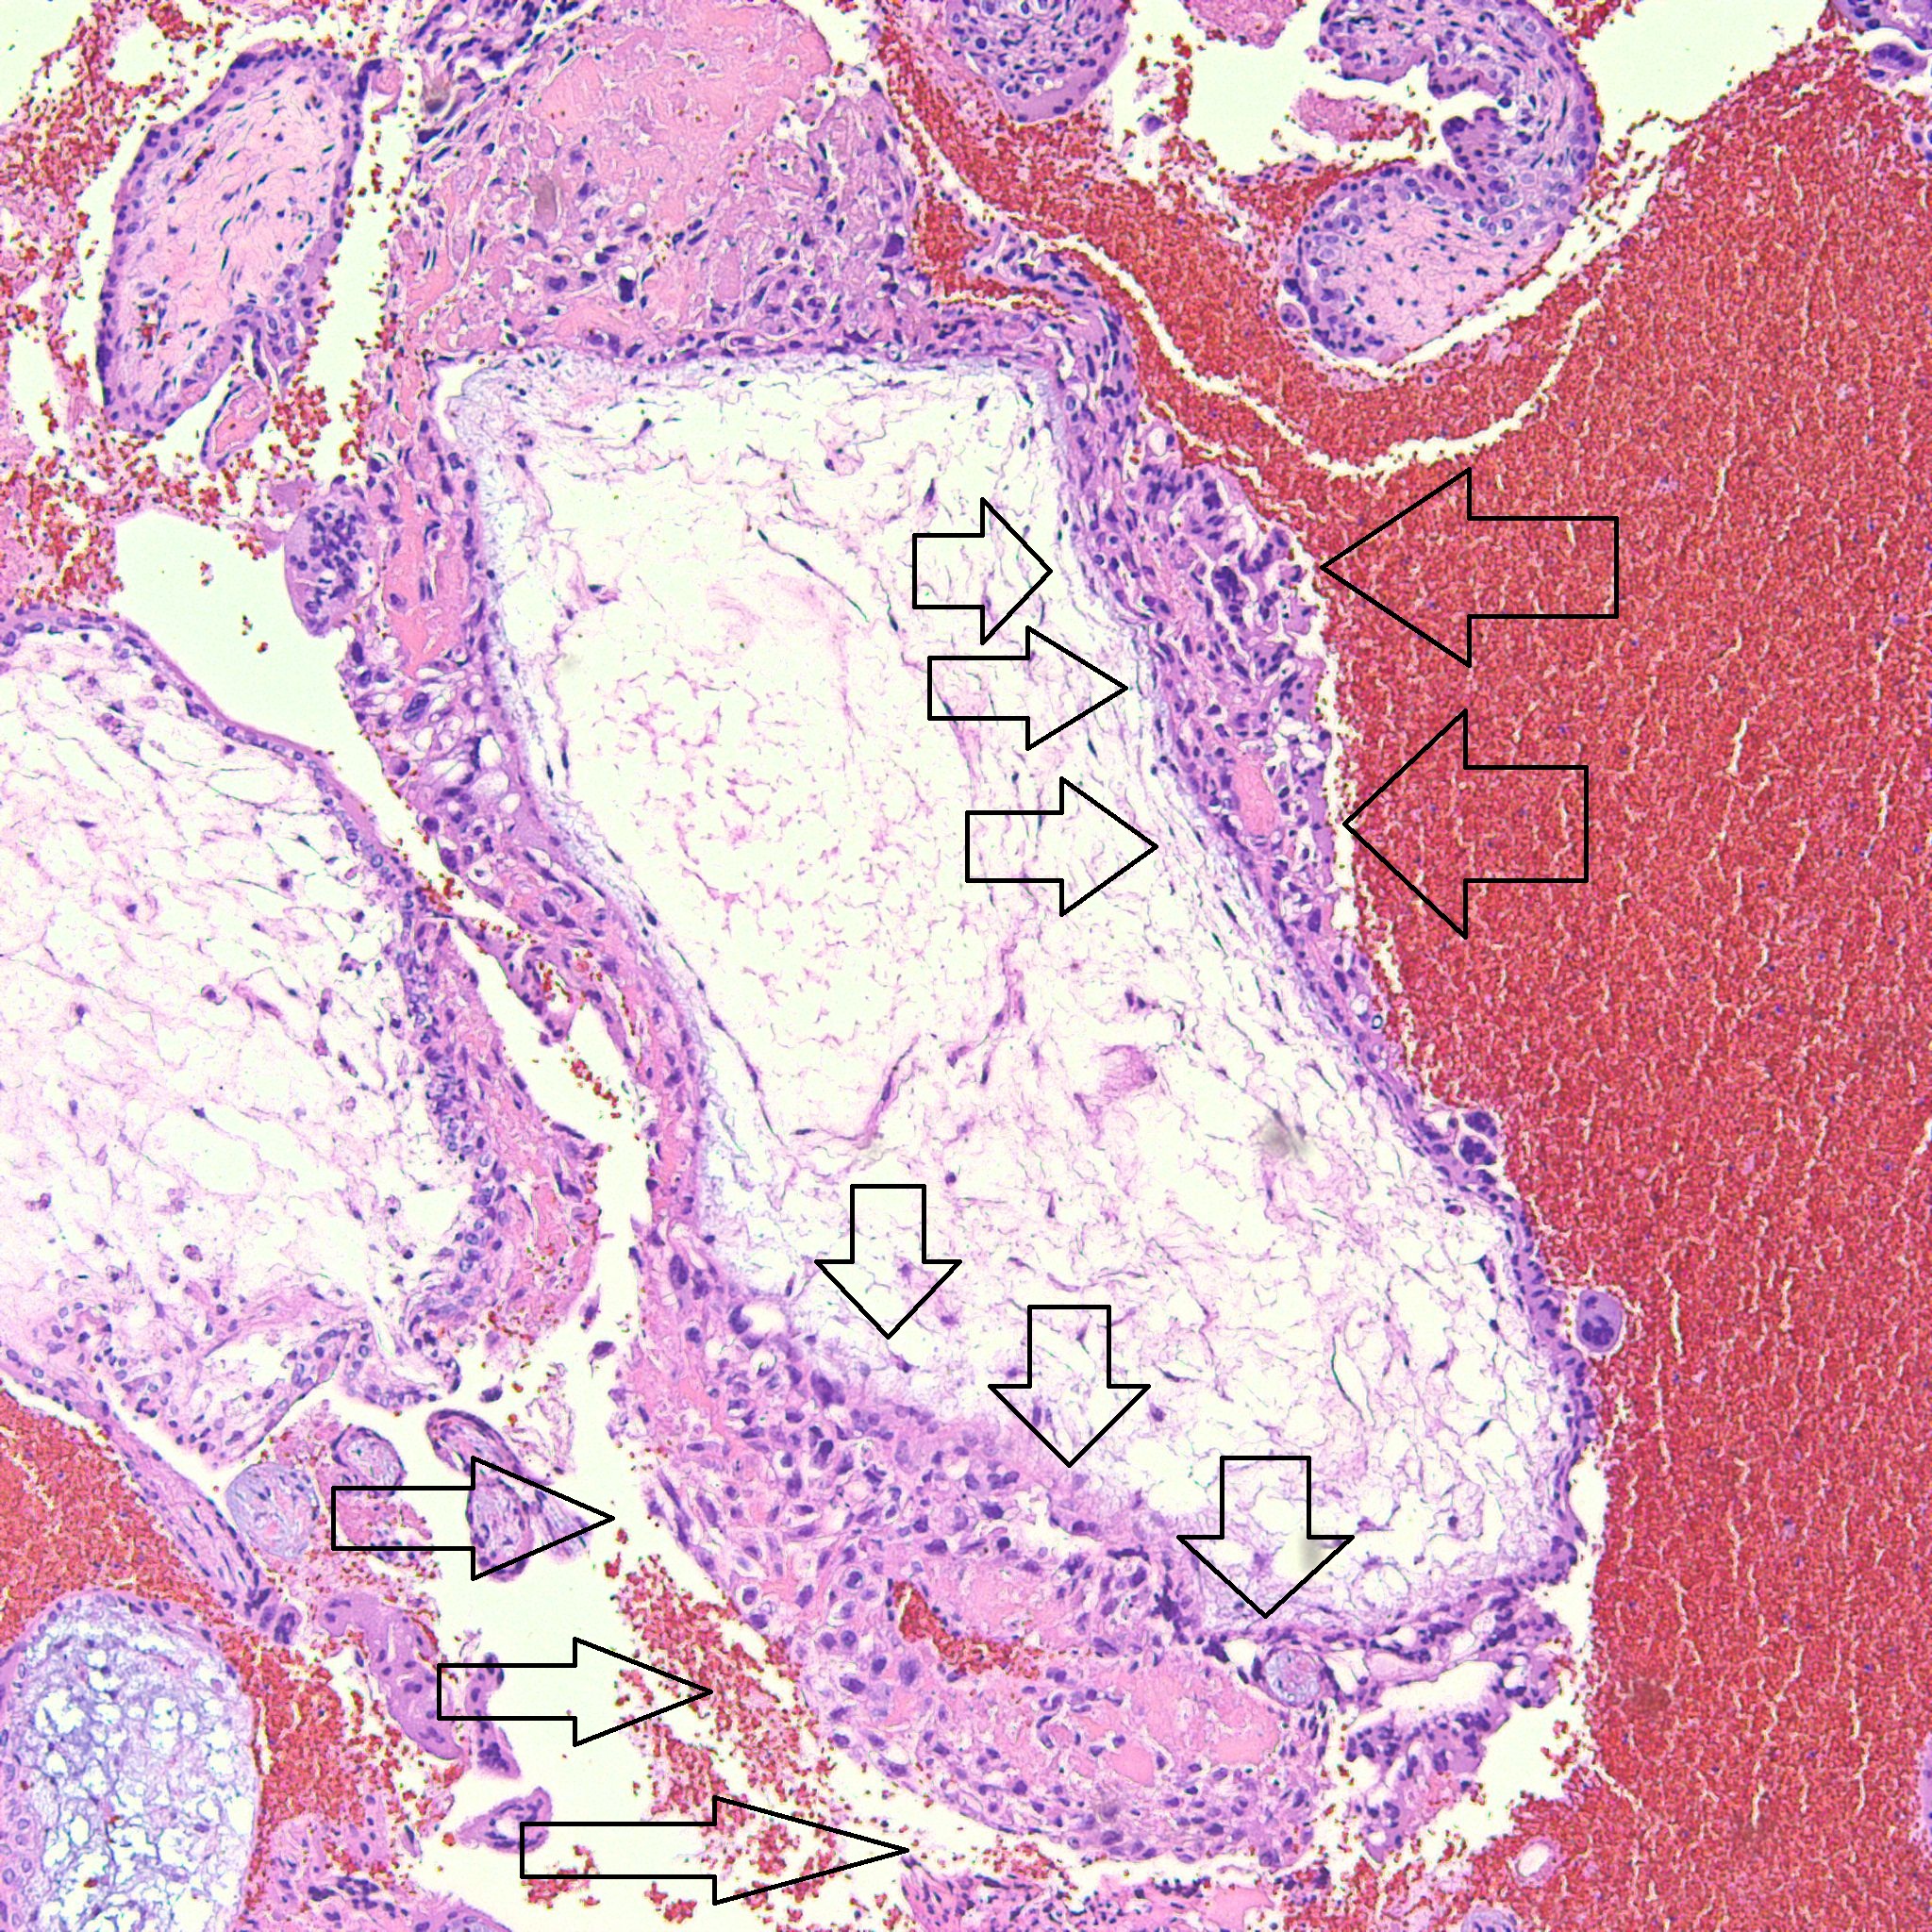

Some villi are so large and hydropic that a few have actually developed central cisterns, spaces within the center of the villi (space highlighted by horizontal lines).

This large hydropic villus with central cistern also demonstrates an important finding: the loss of polarity of the surrounding trophoblasts with circumferential proliferation of variably atypical trophoblastic cells (arrows).